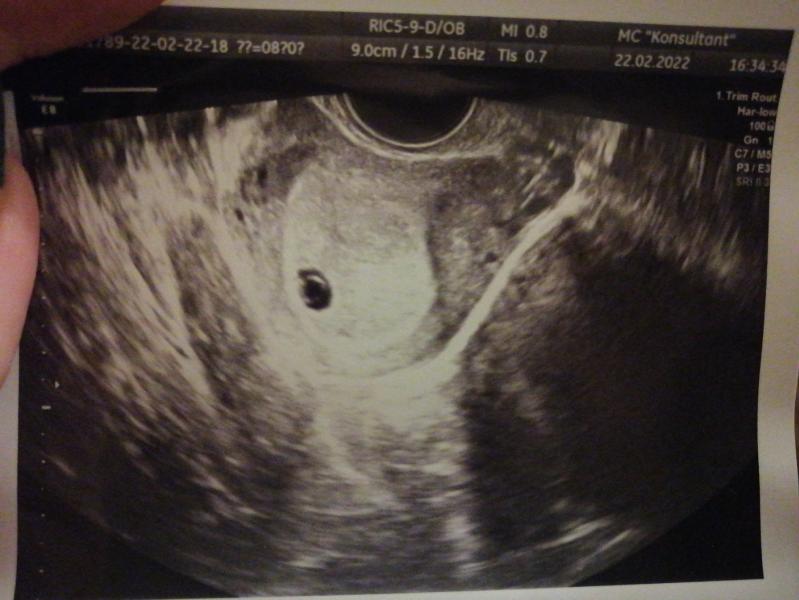

Здравствуйте! Подскажите пожалуйста возможно ли такое, что по месячным срок 8 недель, а по узи 5-6? Ставят замершую под вопросом, первая беременность, 2,5 года не получалось Может у кого-то была такая ситуация и благополучная беременность в итоге?

Сначала эмбрион врач не увидела, потом я разплакалась и он появился на экране и сердечко, плюс сказали матка седловидная

Делала узи 1 марта, увидели эмбрион 2,3мм единичное сердцебиение

По узи поставили 5 недель и 5 дней